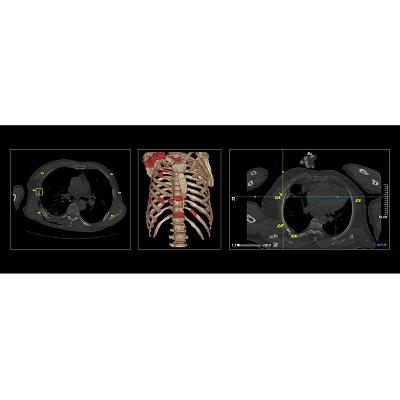

联影智能CT骨折智能分析系统具备“精确定位,秒级骨折检出,直观提示病灶,精细优化工作流”等一系列特点。基于深度学习的方法,自动完成肋骨、椎骨定位与计数,智能完成肋骨、椎骨、锁骨、肩胛骨、胸骨骨折检出与分类。同时,系统还提供MPR三视图、VR图、3D MIP、CPR、SCPR图像的全肋骨展开图、局部动态图等多种阅片视图,一键自动呈现骨折最佳视角,让骨折一目了然,细微骨伤“无处遁形”,辅助医生快速、高效、精准地完成骨折的诊断,避免错诊和漏诊。